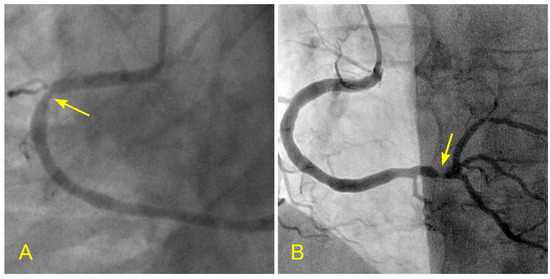

Figure 16.

(A,B) Blood flow across a coronary lesion. These images are in continuous sequence. A middle-aged patient presented with unstable angina and underwent a coronary angiogram. (A). The artery was full of contrast in black. There was a 50% lesion in the mid-segment of the right coronary artery (RCA) (arrowhead). (B) At the ostium of the RCA, the blood, in white, moved in at the beginning of diastole (arrow). (C,D) The blood flow across a coronary lesion. (C) The blood, in white, was now at the beginning of the RCA mid-segment (arrow) (D). The flow of white blood passed the lesion section quickly without disorganized flow (turbulent flow) (arrow). The location of the lesion is marked with an arrowhead. (E,F) The blood flow across a coronary lesion. (E) The blood, in white, was now at the end of the RCA mid-segment (arrow). There was no reversed flow at the lesion site (arrowhead). (F) The flow of white blood entered the distal segment without disorganized flow (turbulent flow, arrow) at the lesion site (arrowhead).

The results showed that patients with baseline laminar flow remained stable, neither developing ACS nor requiring percutaneous or surgical intervention at the two-year follow-up (Figure 16A–F). In contrast, 83% of patients with baseline turbulent flow across a moderate-sized lesion developed ACS within six months. This pilot study suggests the protective effect of laminar flow and an increased risk of plaque rupture due to turbulent flow [23]. Large randomized studies are needed to confirm these observations.